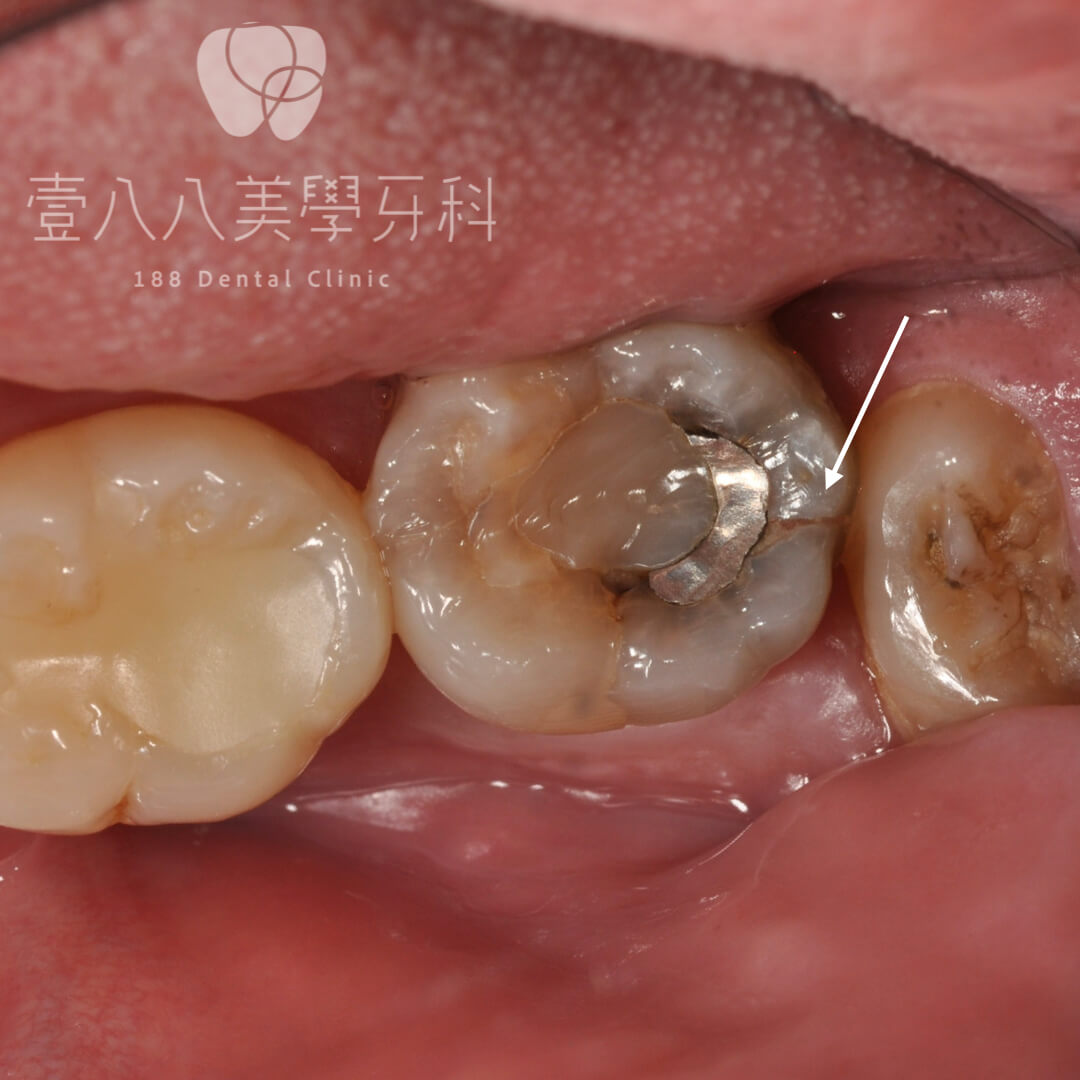

2. 有過大的填補物

過大的填補物,因為是外加填補上去,加上材料本身(複合樹脂)不夠強,所以填補物要建立在相對強健的齒質上才會長久,因此過大的填補物意味原本齒質不夠強壯,容易產生脆弱點進而咬崩或脫落,尤其是根管治療過的,更是容易沿著牙根縱裂而使整個牙齒報銷。

牙齒咬合面不是一個平面,通常有起伏幫助咀嚼效率,但若是起伏較大(牙齒較凹或較尖,見圖示),當咬力一下來就容易產生側方應力,讓牙齒崩落(可能完全沒蛀牙)。